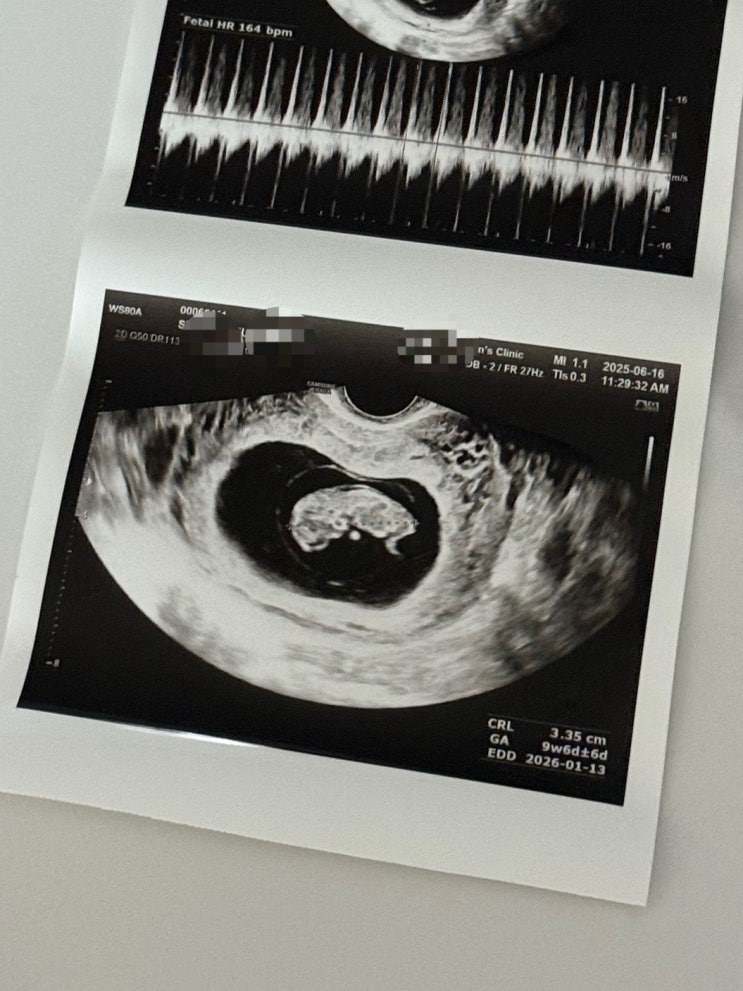

임신 10주 몸무게 입덧 절정 후기

임신 10주 오늘은 임신10주차에 접어들어서 저의 후기를 남겨보려고해요. 아직 초기지만 벌써부터 몸이 많...